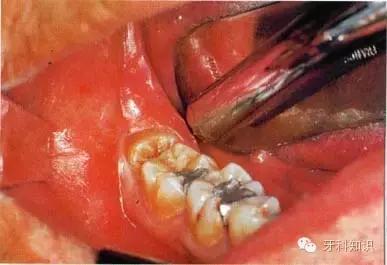

女性患者,40岁。第Ⅰ类,A分类。右下颌第三磨牙阻生,口内可见部分牙冠。黏骨膜瓣切口设计为:远中切口由距离第二磨牙15 mm或更多处开始向前切开,颊侧切口不超过第二磨牙

使用手机上的圆钻显露牙冠最大周径,远中方向显露至釉牙骨质界,颊侧显露至近中颈部

用缝线穿过舌侧软组织并将其拉向舌侧,以避免其受损并保证术区视野清晰。切割牙冠前先将牙根挺松。图示为用合适的牙挺楔入挺松的牙根下面

尽管事先已挺松牙根,但仍无法顺利掏出。于是用纺锤形车针扩大牙槽窝,操作时应紧贴牙槽窝内壁。拔出牙根后可见根尖肥大。这通常与牙骨质增生有关,故不能通过

牙挺施以*力暴**而拔除。术者应尽量避免折裂牙槽窝骨壁